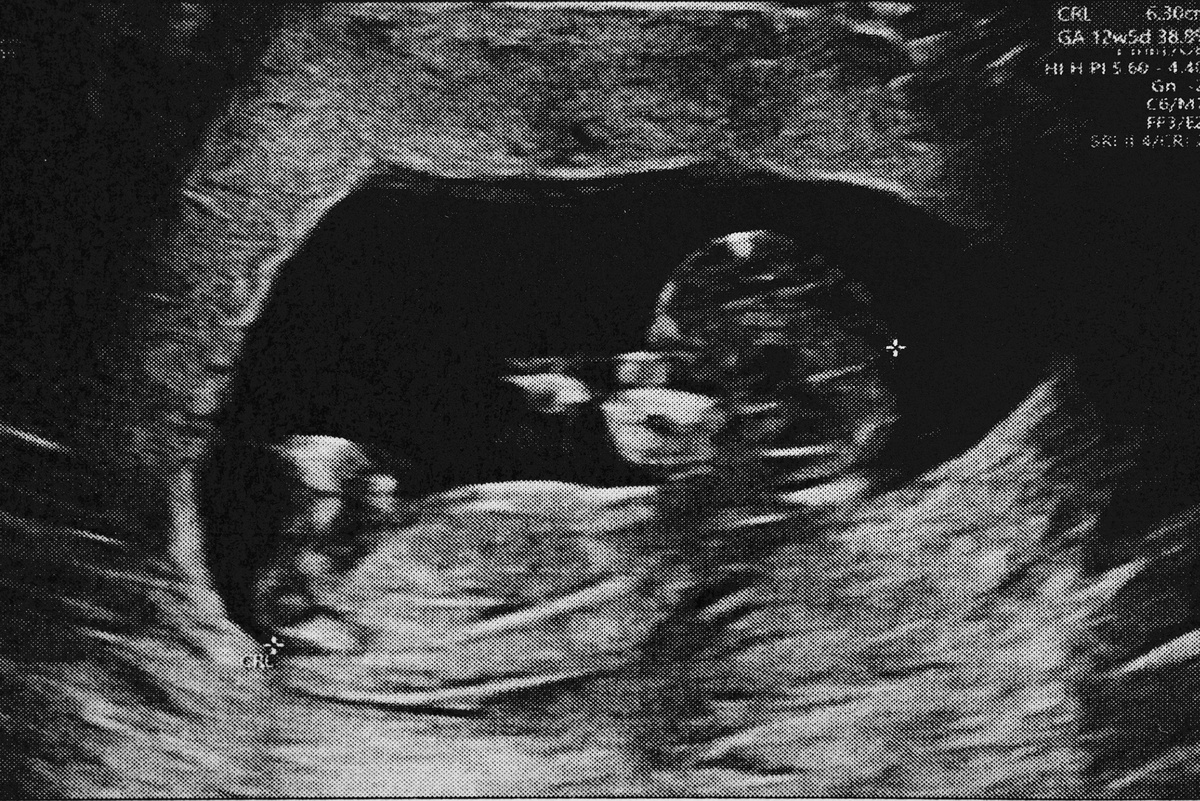

В обязательном порядке беременная пациентка на сроке 18 недель 0 дней — 20 недель 6 дней направляется на ультразвуковое скрининговое исследование по оценке антенатального развития плода с целью выявления хромосомных аномалий, пороков развития, а также оценки расположения, толщины, структуры плаценты, количества околоплодных вод. Также проводится УЗИ шейки матки (УЗ-цервикометрия).

Плод на пятом месяце беременности

В этот период у малыша появляются первые рефлексы. Так, на 17-й неделе появляется рефлекс самосохранения. Проявляется это тем, что при громких звуках ребенок вздрагивает и группируется.

Постепенно тренируются и другие органы и системы. Например, в 18 недель малыш может периодически заглатывать околоплодные воды, которые затем фильтруются через почки и выводятся в виде мочи. Так начинает работать желудочно-кишечный тракт и мочевыделительная система. Кроме того, активно развивается мозг, а рост головы при этом замедляется.

Уже в 20 недель мама может активно ощущать все движения крохи, ведь в этот период вытягиваются ручки и ножки малыша, и он начинает ими активно двигать. А еще он учится моргать, открывая и закрывая глазки!

Плод в 5-й месяц беременности